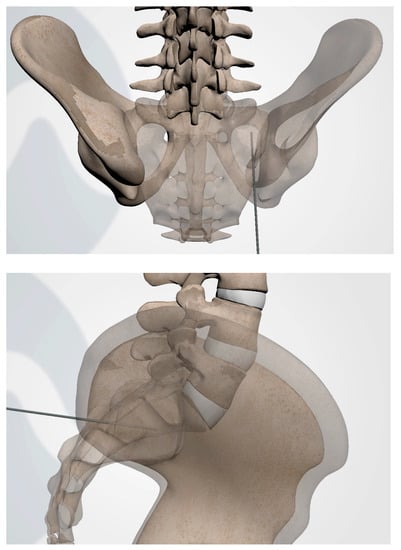

3.3.1. Patient Positioning

3.3.4. Steinman Pin Placement